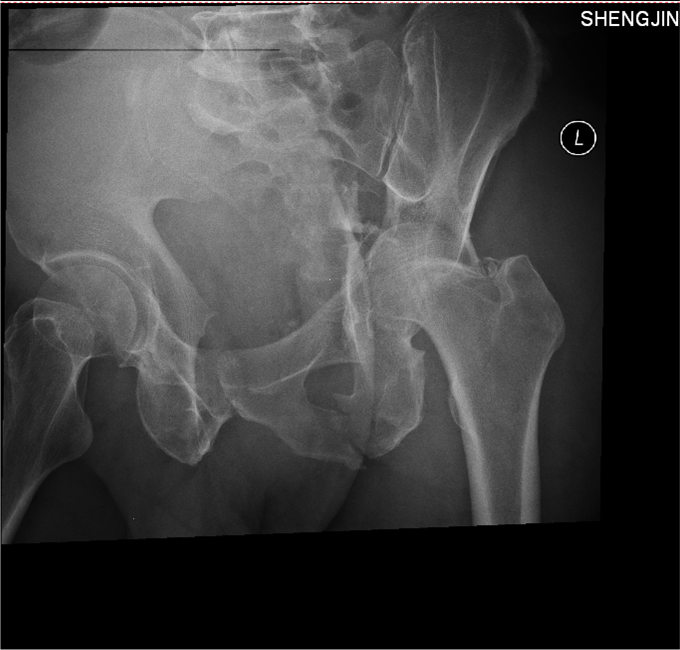

1.患者老年男性,以“车祸左髋部疼痛活动受限3天”为主诉入院。 2.现病史:患者自述于2014-11-04日晚下午7点发生机动车肇事,伤后患者急救车送往孤山二院,诊断为左髋臼骨折,当地医院未经任何治疗。急来中国医科大学附属盛京医院第五骨科创伤骨科治疗。我科以“左髋臼骨折”为主要诊断收入院。今来我院就诊,患者病来一般状态可,生命体征平稳,无发烧无发热,饮食睡眠可。

专科查体:患者平车入病房,左腿内收内旋屈曲畸形,左髋部压痛(+),叩击痛(+),骨盆分离试验阳性,活动受限,双下肢感觉未见异常,活动可,双侧足背动脉搏动可触及,双侧足趾活动灵活。

入院后急诊行左髋关节脱位复位术,左胫骨结节骨骼牵引术。术后牵引7公斤,完善相关检查后,全麻下行左髋臼骨折切开复位内固定术。术后患者生命体征平稳,卧床。术后14天拆线后出院,回当地医院继续治疗。